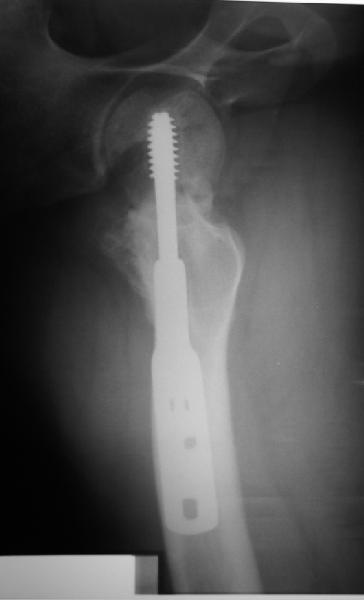

Учитывая возраст больного и качество кости, я однозначно за остеосинтез. Можно обойтись и без остеотомии, линия излома не вертикальная. Возможно с костной аутопластикой для стимуляции. Только отрепонировать хорошо, на представленных снимках, перелом недорепонирован, есть ротационное смещение. Плюс винт биомеханически введен не совсем удачно.

на представленных рентгенограммах прослеживается линия резорбции вокруг введенного винта, что свидетел ствует о нестабильности произведенного остеосинтеза ии отсутствии консолидации перелома. На мой взгляд нужно произвести ркт исследование и выполнить при отсутствии консолидации реостеосинтез с костной аутопластикой. При отсутствии сращения после данной операции остается ввариант с эндопротезированием. Выполнить репозицию несросшегося перелома закрытым способом на мой взгляд не совсем реально, открытая репозиция чревата аваскулярным некрозом. Выполнение вальгизирующей остеотомии считаю нецелесообразным так как это приведет к увеличению давления на головку (за счет натяжения мышц бедра )6 лишенную нормального кровотока приведет к ее коллабированию. С уважением Даниленко Олег.

Никто не обратил внимания, что конструкция-то вся "развинчена" - вывернулся винт из шеечного винта, пластина не прилегает к диафизу. Резорбция кости вокруг шеечного винта не позволит как-нибудь надежно синтезировать вальгизирующую остеотомию, а в случае неудачи сама остотомия осложнит последующее эндопротезирование. Поэтому, думаю, что лучшим вариантом будет синтез аутокостью + канюлированные винты (дабы избежать кокситной повязки).

Похоже удалось провести шеечный винт мимо старого канала, и вальгус, вроде, удался. Только хороший-ли контакт фрагментов в зоне остеотомии? Действительно - жизнь покажет.